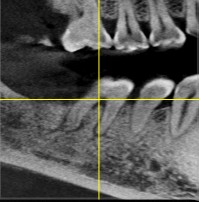

患者男,五十岁,右下后牙咬合不适,前来外院就诊。X线片显示46根尖部有阴影。口内检查发现,颌面大面积树脂充填物,周边有继发性龋坏。探-,叩+,余无不适。治疗计划:根管治疗后高嵌体修复。

术前